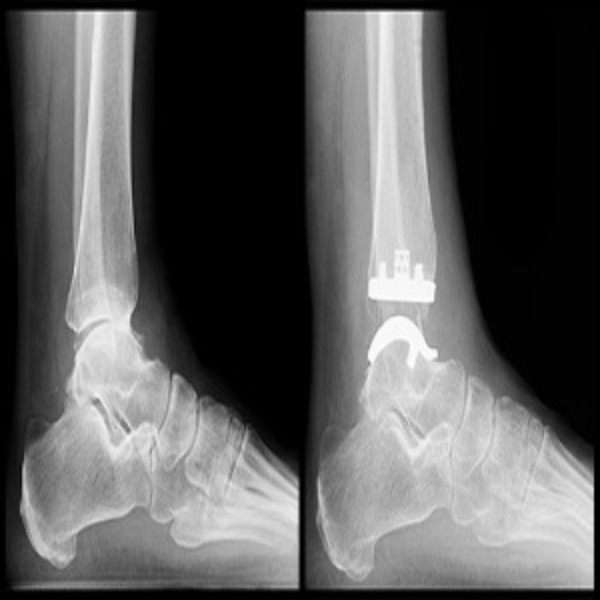

Best Hospital For Ankle Replacement Surgery Near Me